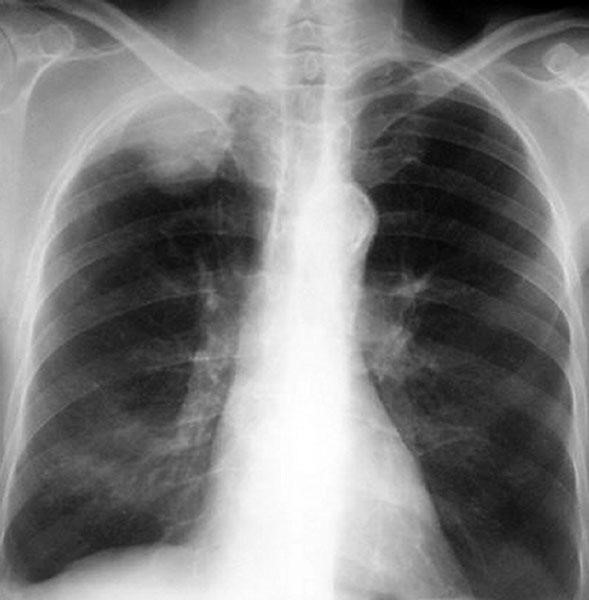

Диагностика заболевания заключается в следующем:

- выявление первичного очага (в случае наличия нескольких — выбор наибольшего);

- определение его размеров, наличия капсулы, прорастания в окружающие ткани;

- выявление лимфатических узлов, вовлеченных в процесс;

- выбор контрольной группы (очаг + лимфоузлы) для оценки динамики развития процесса или результатов лечения;

- определение гистологической структуры и биохимического состава опухоли;

- поиск отдаленных метастазов;

- выбор правильной тактики лечения в зависимости от вышеперечисленных факторов.

Что пишут в КТ при раке легких?

На снимках КТ можно обнаружить опухоль, скопление жидкости или увеличенные лимфатические узлы еще до появления симптомов. Рентген грудной клетки и цитологическое исследование мокроты не считаются методами скрининга диагностики рака лёгких. Важно знать, что скрининг нужен не всем.